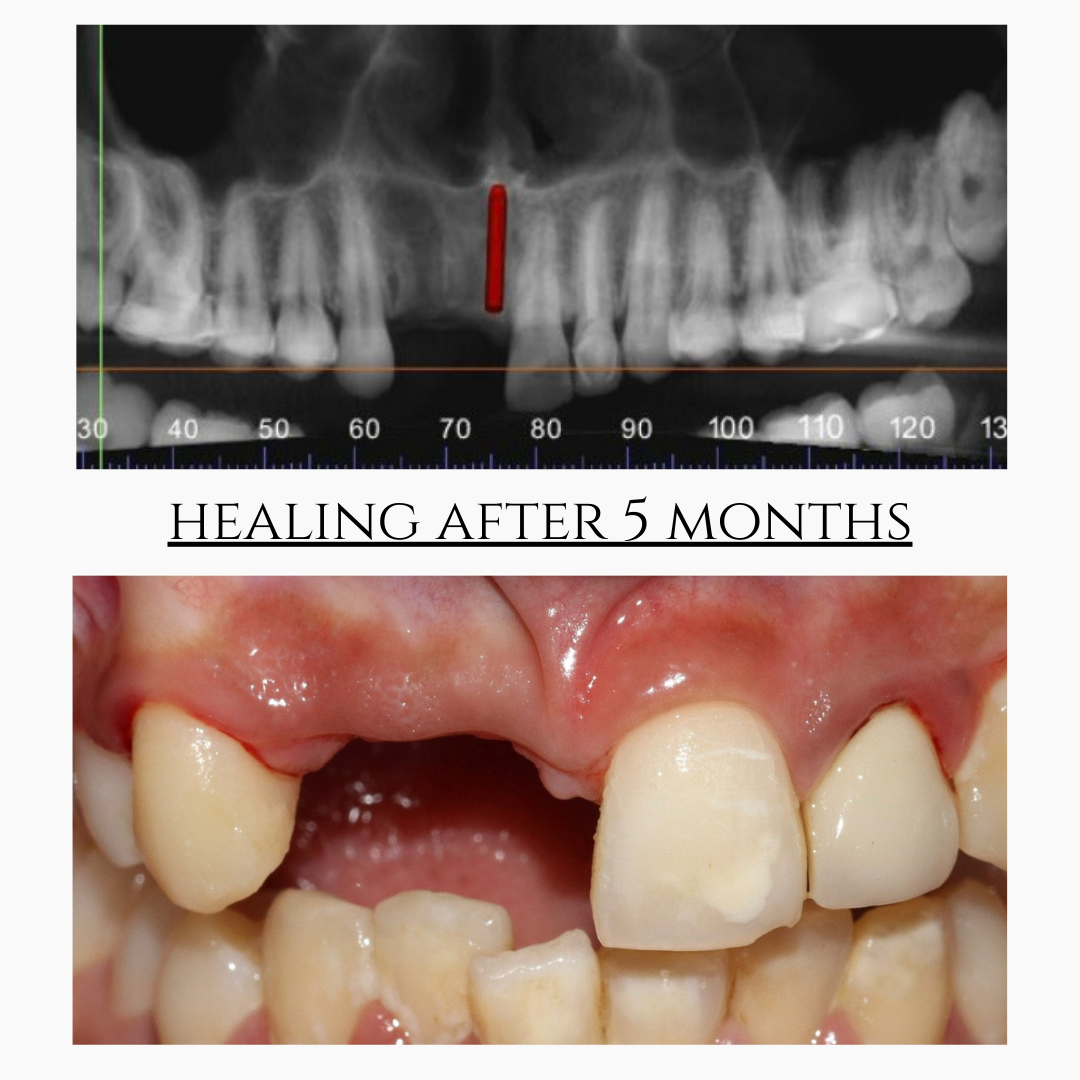

Bone grafting or sinus lift procedures are recommended when there is insufficient bone to support dental implants.

Our clinic uses advanced digital implant dentistry, guided by one of Pune's top expert dentists, including CBCT 3D scans, intraoral scanners, and precision-guided planning to ensure accurate implant placement, faster healing, and predictable results.